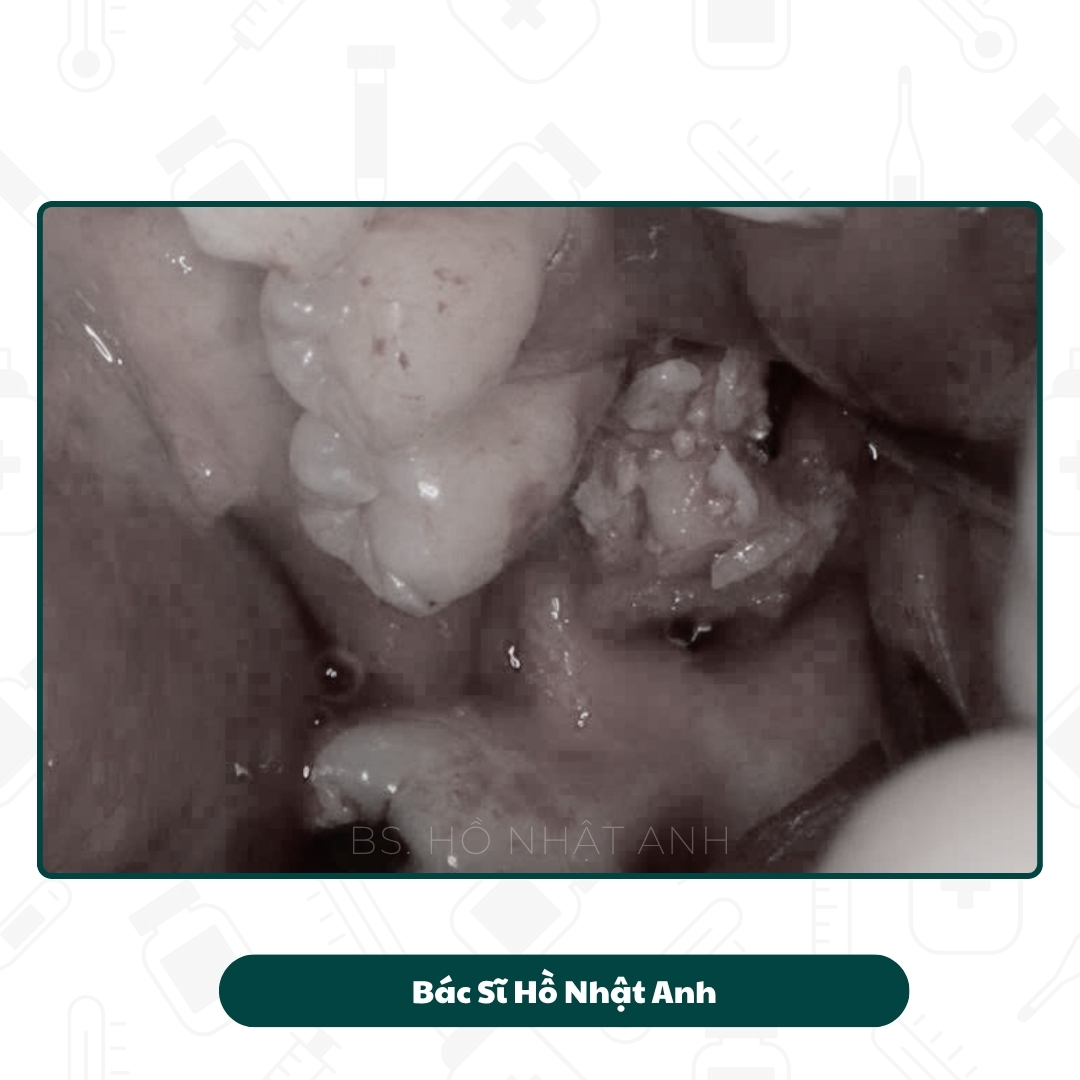

Quy Trình Cắm Implant, Ghép Xương Carotta Và Lên Răng

Quy Trình Cắm Ghép Implant

Quy trình cắm Implant, Ghép xương, xử lý mô mềm Và Lắp răng